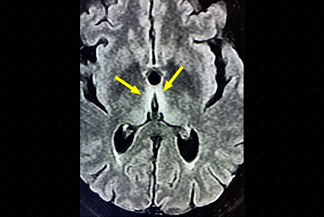

Texto alternativo para a imagem Figura 2. Créditos: Dra. Elazir Mota - Rio de Janeiro/RJ

Descrição da figura 2: Mesmo paciente da figura 1, ressonância magnética do crânio, sequência T2, evidenciando hipersinal bilateral e simétrico na porção medial dos tálamos (setas amarelas). Paciente com diagnóstico de encefalopatia de Wernicke, logo após a ressonância, iniciou reposição de Tiamina.

• Ressonância magnética do crânio: Diante dessa suspeita clínica, o exame de escolha deve ser a ressonância magnética por ser o único método capaz de detectar as alterações de sinal no parênquima. Observam-se áreas de hipersinal simétricas e bilaterais no T2 e FLAIR nas porções mediais do tálamo (85%), corpos mamilares (58%), teto mesencefálico ou placa quadrigeminal (35%), região periaquedutal e ao redor do 3 o ventrículo.